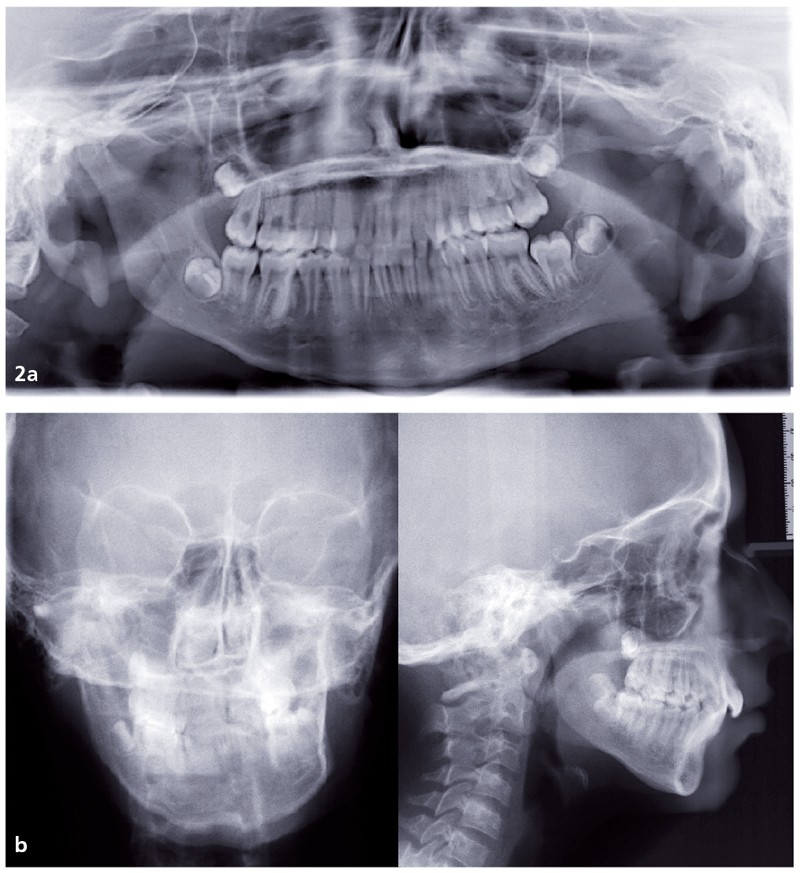

Analyse squelettique : les documents montrent une classe II squelettique modérée par rétrognathie mandibulaire dans un contexte de normodivergence. Les examens complémentaires confirment que la latérognathie mandibulaire gauche est la conséquence d’un hypo-développement des structures maxillaires et mandibulaires de ce même côté (fig. 2a, b et c). On observe sur les reconstructions 3D (à partir des coupes scanner) à l’aide du logiciel Osirix® : un corps mandibulaire fin, un ramus peu développé, un col du condyle grêle.